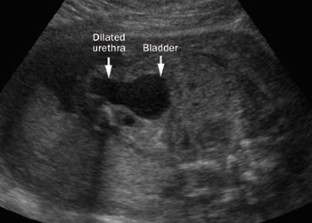

Robyr, R. et al. Correlation between ultrasound and anatomical findings in fetuses with lower urinary tract obstruction in the first half of pregnancy. Ultrasound Obstet. Gynecol. 25, 478–482 (2005).

Bernardes, L. S. et al. Keyhole sign: how specific is it for the diagnosis of posterior urethral valves? Ultrasound Obstet. Gynecol. 34, 419–423 (2009).